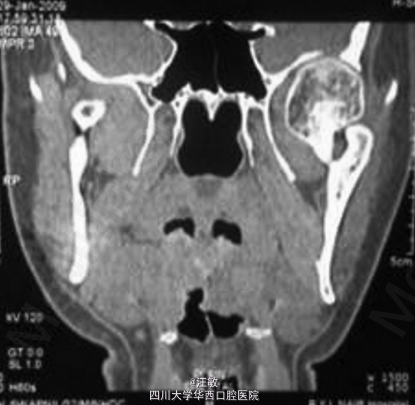

综合临床和影像诊断为左侧髁突骨软骨瘤

病例中患者有明显的面部不对称,但是全景片并未发现有明显异常。此时计算机断层扫描可以帮助临床医生更加准确的确定病损区域。有趣的是病例中CT扫描可以明显发现左侧髁突增大,但是三维重建却发现左髁突外观正常。 doi:org/10.1016/j.jobcr.2014.12.001